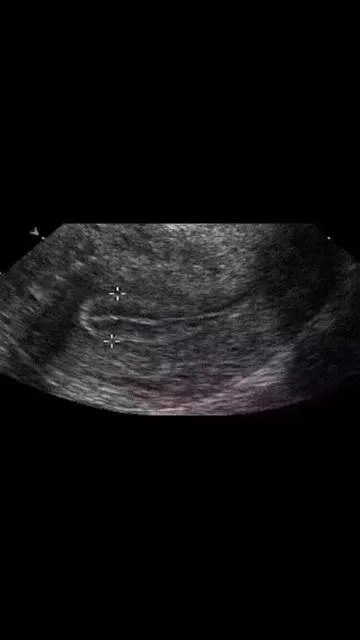

在平時進行內膜檢測過程中,醫生常會說到內膜太薄、太厚、不均質、有強光團,或內膜形態不好、三線不清、內膜線中斷等等。

以上這些情況不利于胚胎著床和發育,不適宜移植新鮮胚胎,建議做一下宮腔鏡檢查,排除子宮內膜息肉、宮腔粘連、慢性子宮內膜炎癥、內膜過度增生,以及雙角子宮、單角子宮、子宮縱膈等等的病變,并進行相應的治療。等內膜的病變去除,宮腔形態恢復以后再予以移植為好。